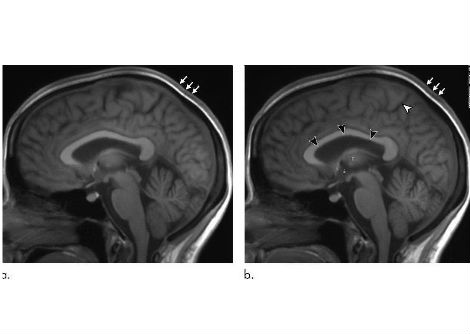

يمكن للطبيعة الدائرية لـ ecDNAs تمكين التفاعلات الجينية التي قد تدعم زيادة نسخ الجينات الورمية ، حيث قد تتفاعل العناصر الجينية الموجودة عادة في أجزاء بعيدة من الجينوم معًا. في حين أن العوازل في الحمض النووي الصبغي تقع في جذع بنية الحلقة وتضمن أن التسلسلات التنظيمية مثل المعززات تعمل فقط على الجينات المستهدفة القريبة ، فإن الشكل الدائري للـ ecDNA يولد تفاعلات جديدة مع تسلسلات تنظيمية إضافية لا تحدث عادة على الحمض النووي الصبغي. .

يمكن أن تدعم العناصر التنظيمية الإضافية تعبير الجين الورمي العالي.